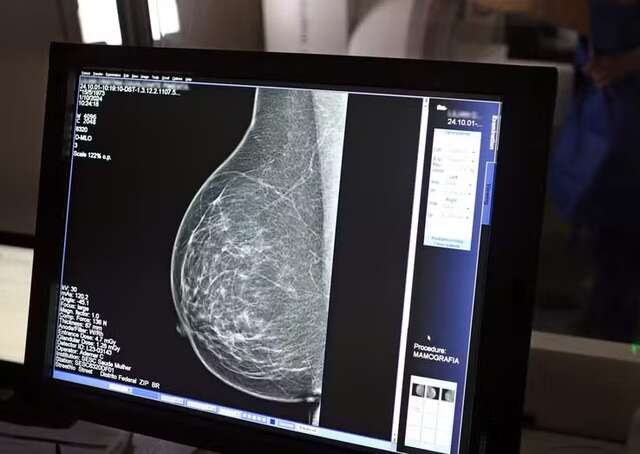

A inteligência artificial pode ser utilizada para prever o risco de doenças cardiovasculares em mulheres a partir de análises de mamografias.

Segundo a pesquisa, a IA consegue avaliar o acúmulo de depósitos de cálcio nas artérias da mama a partir dos exames de raio-x, muito utilizados para o rastreamento de câncer.

A calcificação arterial das mamas costuma ser identificada em mamografias de rotina e não tem relação com tumores. Mas, diversos estudos mostram a associação da calcificação com fatores de risco cardiovascular e futuro desenvolvimento de doenças cardíacas.